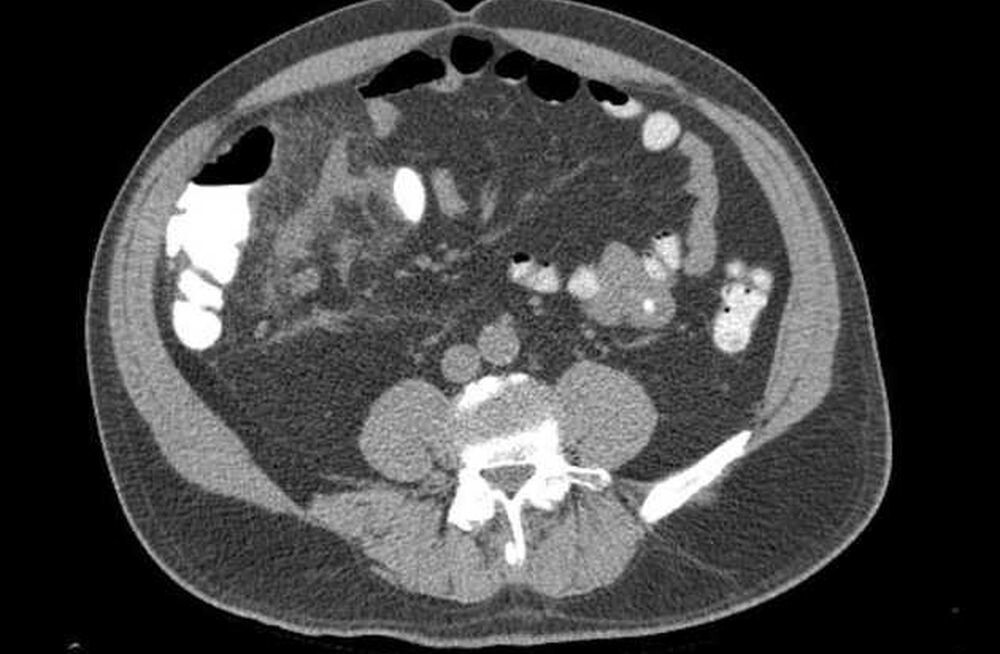

Задачка не из легких досталась врачам города Балаково Саратовской области, когда к ним поступил юный пациент с сильно избыточным весом и диагнозом острый флегмозный аппендицит. Хирургические вмешательства при таком анамнезе чреваты осложнениями, так как сильное ожирение нарушает работу сердечно-сосудистой, дыхательной, эндокринной систем, печени и почек. Помимо этого у подростка наблюдался высокий уровень сахара в крови, что указывает на возможное развитие преддиабета.

Хирургическое вмешательство осуществлялось посредством высокотехнологичной лапароскопической аппендэктомии. Все закончилось благополучно и пациент уже идет на поправку. Как говорится, попал в золотые руки.